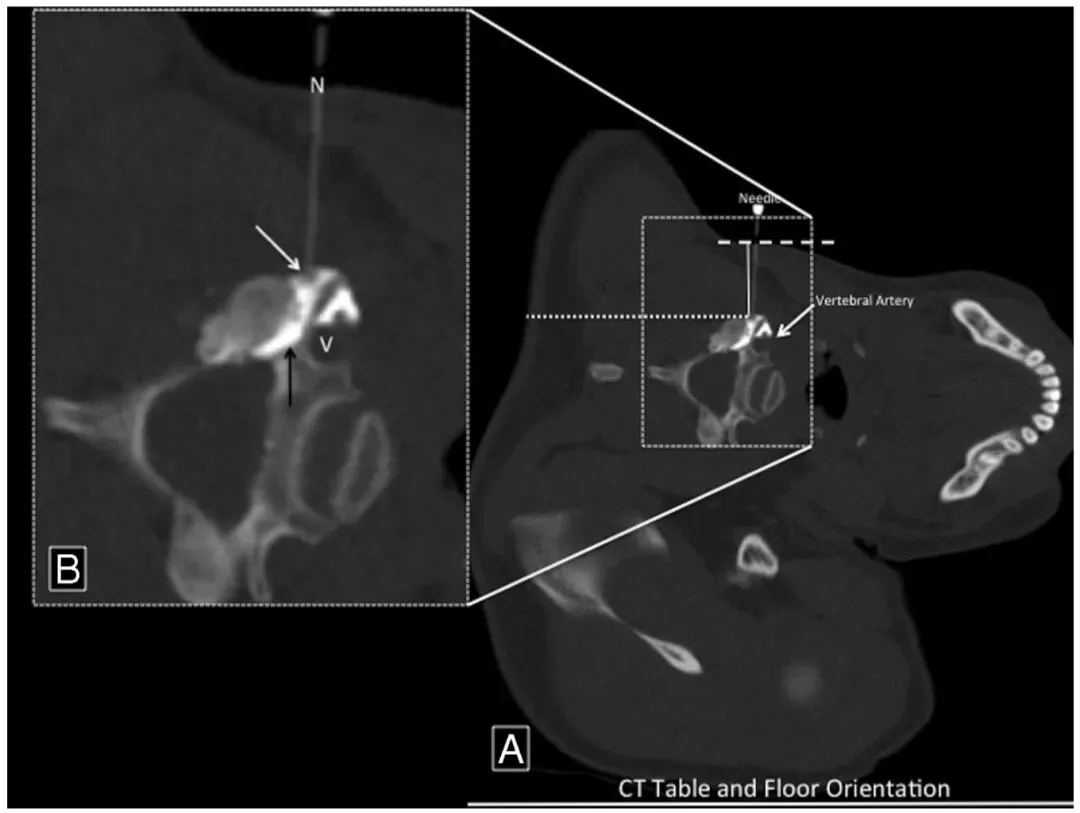

4. 穿刺路径规划:在CT控制台上绘制近乎垂直于靶神经孔的穿刺路径,测量皮肤到靶点的距离。采用侧方入路,垂直地面的进针方向。

5. 穿刺针选择:大部分病例选用2.5 cm长、25G穿刺针。全组105例使用此规格,11例因靶点位置较深换用7.5 cm脊髓穿刺针。

6. 针尖位置确认与调整:穿刺针插入至预定深度后,以活检扫描模式获取靶区影像,重建5层2.5 mm薄层图像(序列2),确认针尖与靶点的相对位置。若位置不满意,调整针尖后再次扫描确认(序列3),重复此过程直至针尖精准到位。

7. 注射前安全确认:先缓慢注入1 mL稀释的碘海醇混合1%利多卡因,通过影像和临床表现判断有无血管内误注。确认神经功能无变化后,再缓慢推注地塞米松类固醇药物。术中及术后即刻全程监测患者神经功能状态和生命体征。